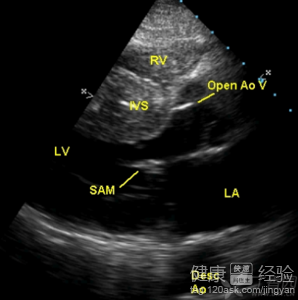

1該病的發生主要是由於化妝的心室雙側已經出現了明顯的擴大跡象,這時候就很容易導致患者的心室收縮功能減退,伴或不伴充血性心力衰竭,室性或房性心律失常多見。病情呈進行性加重,死亡可發生於疾病的任何階段。